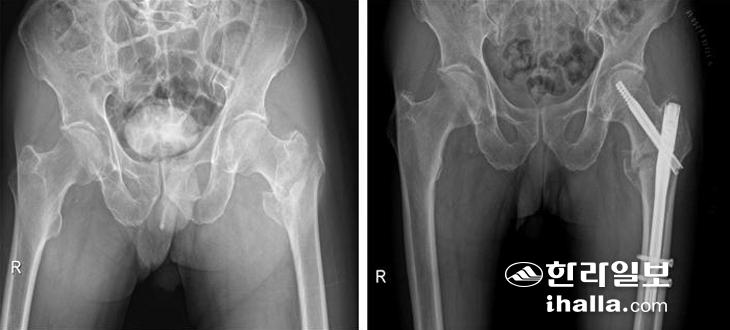

고관절 골절 중에서도 부러진 위치에 따라서 구분을 하는데 이는 골절 위치에 따라 수술 방법이 달라지기 때문이다. 대퇴골두 바로 밑의 대퇴골 경부 골절의 경우에는 골두로 가는 혈액순환이 끊어질 가능성이 높아 뼈를 붙이는 수술을 하더라도 잘 붙지 않을 수 있다. 설령 붙었다 하더라도 대퇴골두 무혈성 괴사가 발생하게 되면 지속적인 통증이 남는다. 이러한 이유로 인공관절 수술을 하는 경우가 많다. 단, 골절의 전위가 심하지 않거나 불완전 골절인 경우, 그리고 젊은 환자에서는 뼈를 붙이는 수술을 해볼 수 있다. 고관절 인공관절 치환술은 8~9cm 피부절개로 근육, 혈관, 신경 등의 조직 손상을 최소화하여 빠른 회복을 도모할 수 있으며 수술 후 안정적일 경우 3~4일이 지나면 걸을 수 있다. 그러나 수술 후 약 3개월 정도는 탈구의 위험이 있을 수 있어 쪼그려 앉기, 양반다리, 다리를 꼬는 행동을 삼가야 하며 이후에는 무리 없이 일상적인 생활이 가능하다.

▶전자간 골절 땐 내고정 수술 시행=대퇴골 경부보다 아래쪽의 대전자와 소전자를 연결하는 부분이 부러지게 되면 전자간 골절이라고 하며 인공관절로 보다는 골수정 또는 금속판을 이용한 내고정 수술을 시행하게 된다.

내고정 수술

이 부위는 대퇴골두 무혈성 괴사가 잘 발생하지 않으며, 비교적 뼈가 잘 붙는 부위다. 수술 후 3~4일 후부터 운동을 조금씩 시작하면서 고관절 주위의 근육을 강화시키는 재활을 시작한다. 과도한 운동은 고정시킨 골수정 또는 금속판이 파손될 위험이 있으므로 지양해야 하고 뼈가 약하거나 분쇄골절이 있는 경우는 6주간은 체중부하를 하지 않고 지팡이나 목발을 사용해야 한다.